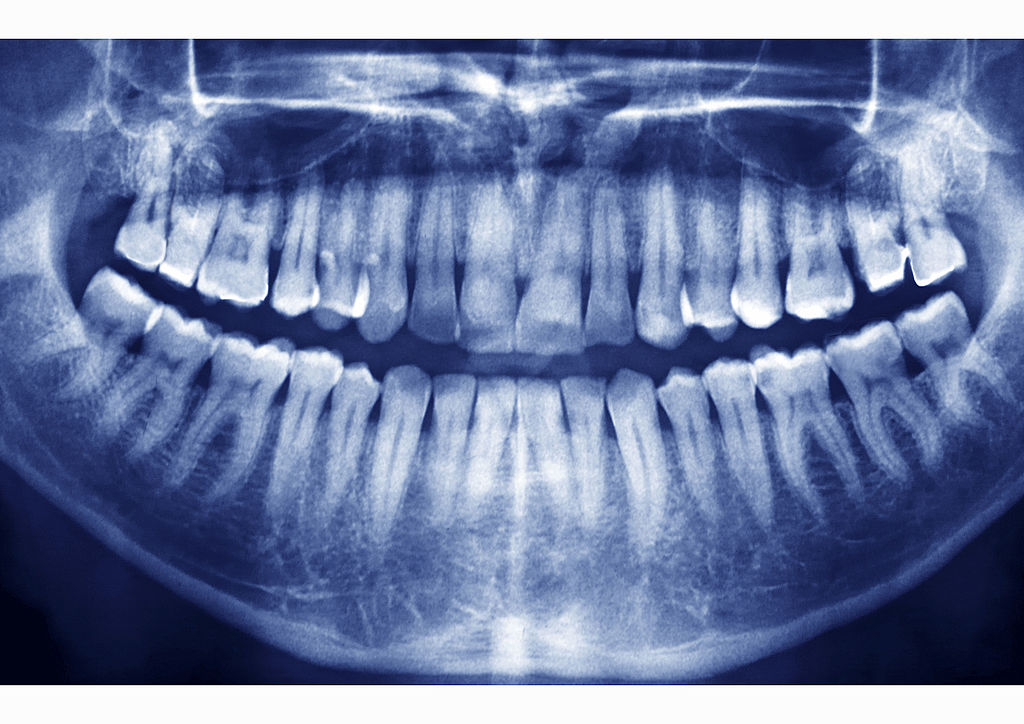

Даже если «восьмерка» не доставляет заметного дискомфорта, она может спровоцировать ряд проблем. На основании рентгенографии врач-стоматолог выявит возможные риски и определит показания к удалению зуба.

Поэтому удаление зависит от анатомической формы этого зуба», — отметила Воронец и добавила, что хирург-стоматолог проводит рентгеновское обследование, чтобы увидеть, как расположен зуб и насколько может быть сложная операция его удаления.

Возможное расположение зубов мудрости в десне:

«У зуба может быть и горизонтальное положение, в таком случае он никогда не прорежется и его удаление будет очень сложным. Если зуб мудрости растет под углом к седьмому, то для такого зуба в челюсти очень мало места, она начинает давить на седьмой зуб, где может образоваться кариес. Поэтому такие зубы рекомендуется удалять», — рассказала стоматолог.

Кости нижней челюсти настолько массивные и плотные, что нормально захватить и раскачать зуб мудрости нереально. Тем более, если над поверхностью десны находится только его часть – стандартная ситуация при затрудненном прорезывании. Даже если коронковая часть развита и хорошо сохранилась, расшатать зуб в массиве мощной кости проблематично, ведь он, как правило, имеет разветвленную корневую систему с непредсказуемым ее расположением в челюсти. Изогнутые 2-3 корня препятствуют извлечению даже расшатанного зуба. Поэтому диагностику хирург-стоматолог проводит на основании рентгеновского снимка.

Особенности строения и расположения зубов мудрости

Зуб мудрости – 8-й в ряду и 3-й из моляров, основное предназначение которых состоит в механической переработке употребляемой нами пищи. У третьего моляра 4 бугра на жевательной поверхности коронки, а также 2,4 или 5 корней с тремя-пятью каналами сложной, изогнутой формы. Иногда корни восьмерки срастаются в один массивный корень, что можно определить лишь при помощи рентгеновского снимка.